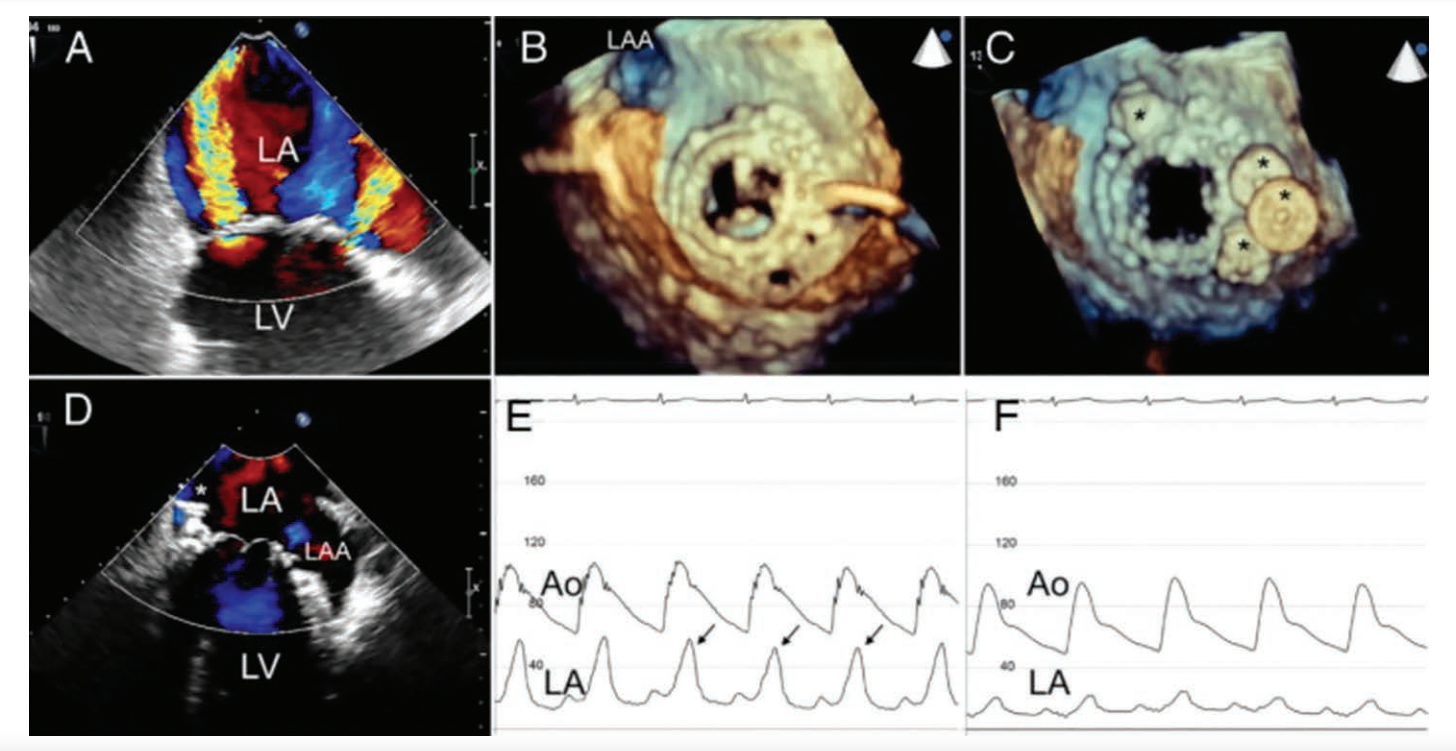

MR Confounder: The Perivalvular Regurgitant Jet

‘V’ waves can result from high regurgitant flow across the mitral valve or flow around a recently implanted valve with a large perivalvular leak. The pressure waves look identical as the mechanisms are nearly identical. Nkomo et al8 present a beautiful demonstration of a large ‘v’ wave of a perivalvular leak (Figure 9). Four Amplatzer vascular plugs (Abbott Vascular) were deployed to close the posteromedial and anterolateral leaks. A marked reduction in paravalvular prosthetic MR with significant hemodynamic reduction of the large ‘v’ wave post procedure was seen. Percutaneous device closure is an effective procedure for the treatment of clinically significant paravalvular prosthetic regurgitation.